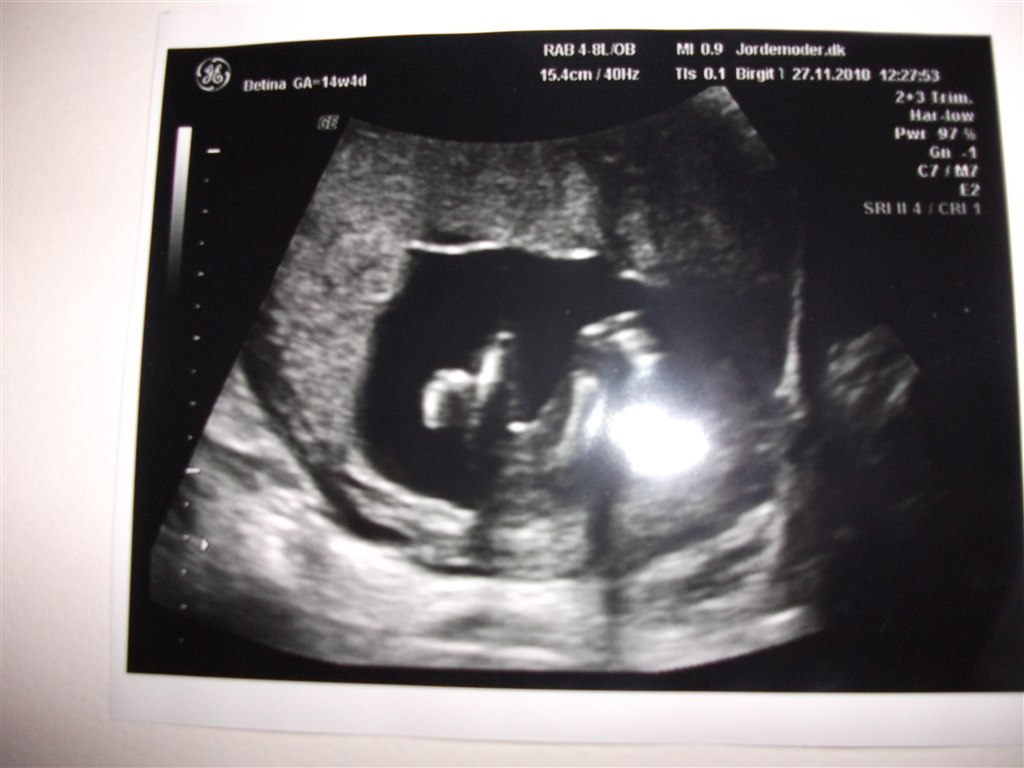

har været til kønsscanning og jordemoderen sagde hun ikke var i tvivl, hvad siger i det er?

haah flot, det skulle have været ano, der står jo på min profil hvad det er, men min computer fuckede lige op.. når vedhæfter alligevel billederne.

Vedhæftede fotos (klik for at se i fuld størrelse)

Jeg blev selv scannet 30 gange sidste gang, men jeg kan ikke rigtig se hvad der er hvad på de billeder...

en bette PIGE

det er mit gæt